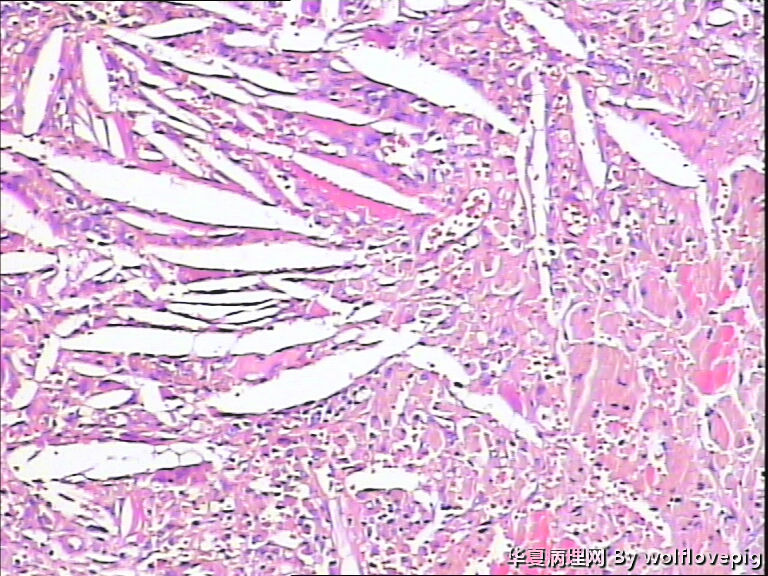

男,70y,左腰痛一年,反复血尿1月,坐肾区轻叩痛。

• 求助!肾脏包块!图3

图3

大体图片有些让人担心。镜下图片更倾向是良性病变。主要为对坏死组织的反应。

图片质量非常不好,显微镜下的图片几乎没法观察, 看大体标本还是不能除外肿瘤性病变,能不能采一些高质量的图片?

炎症性病变